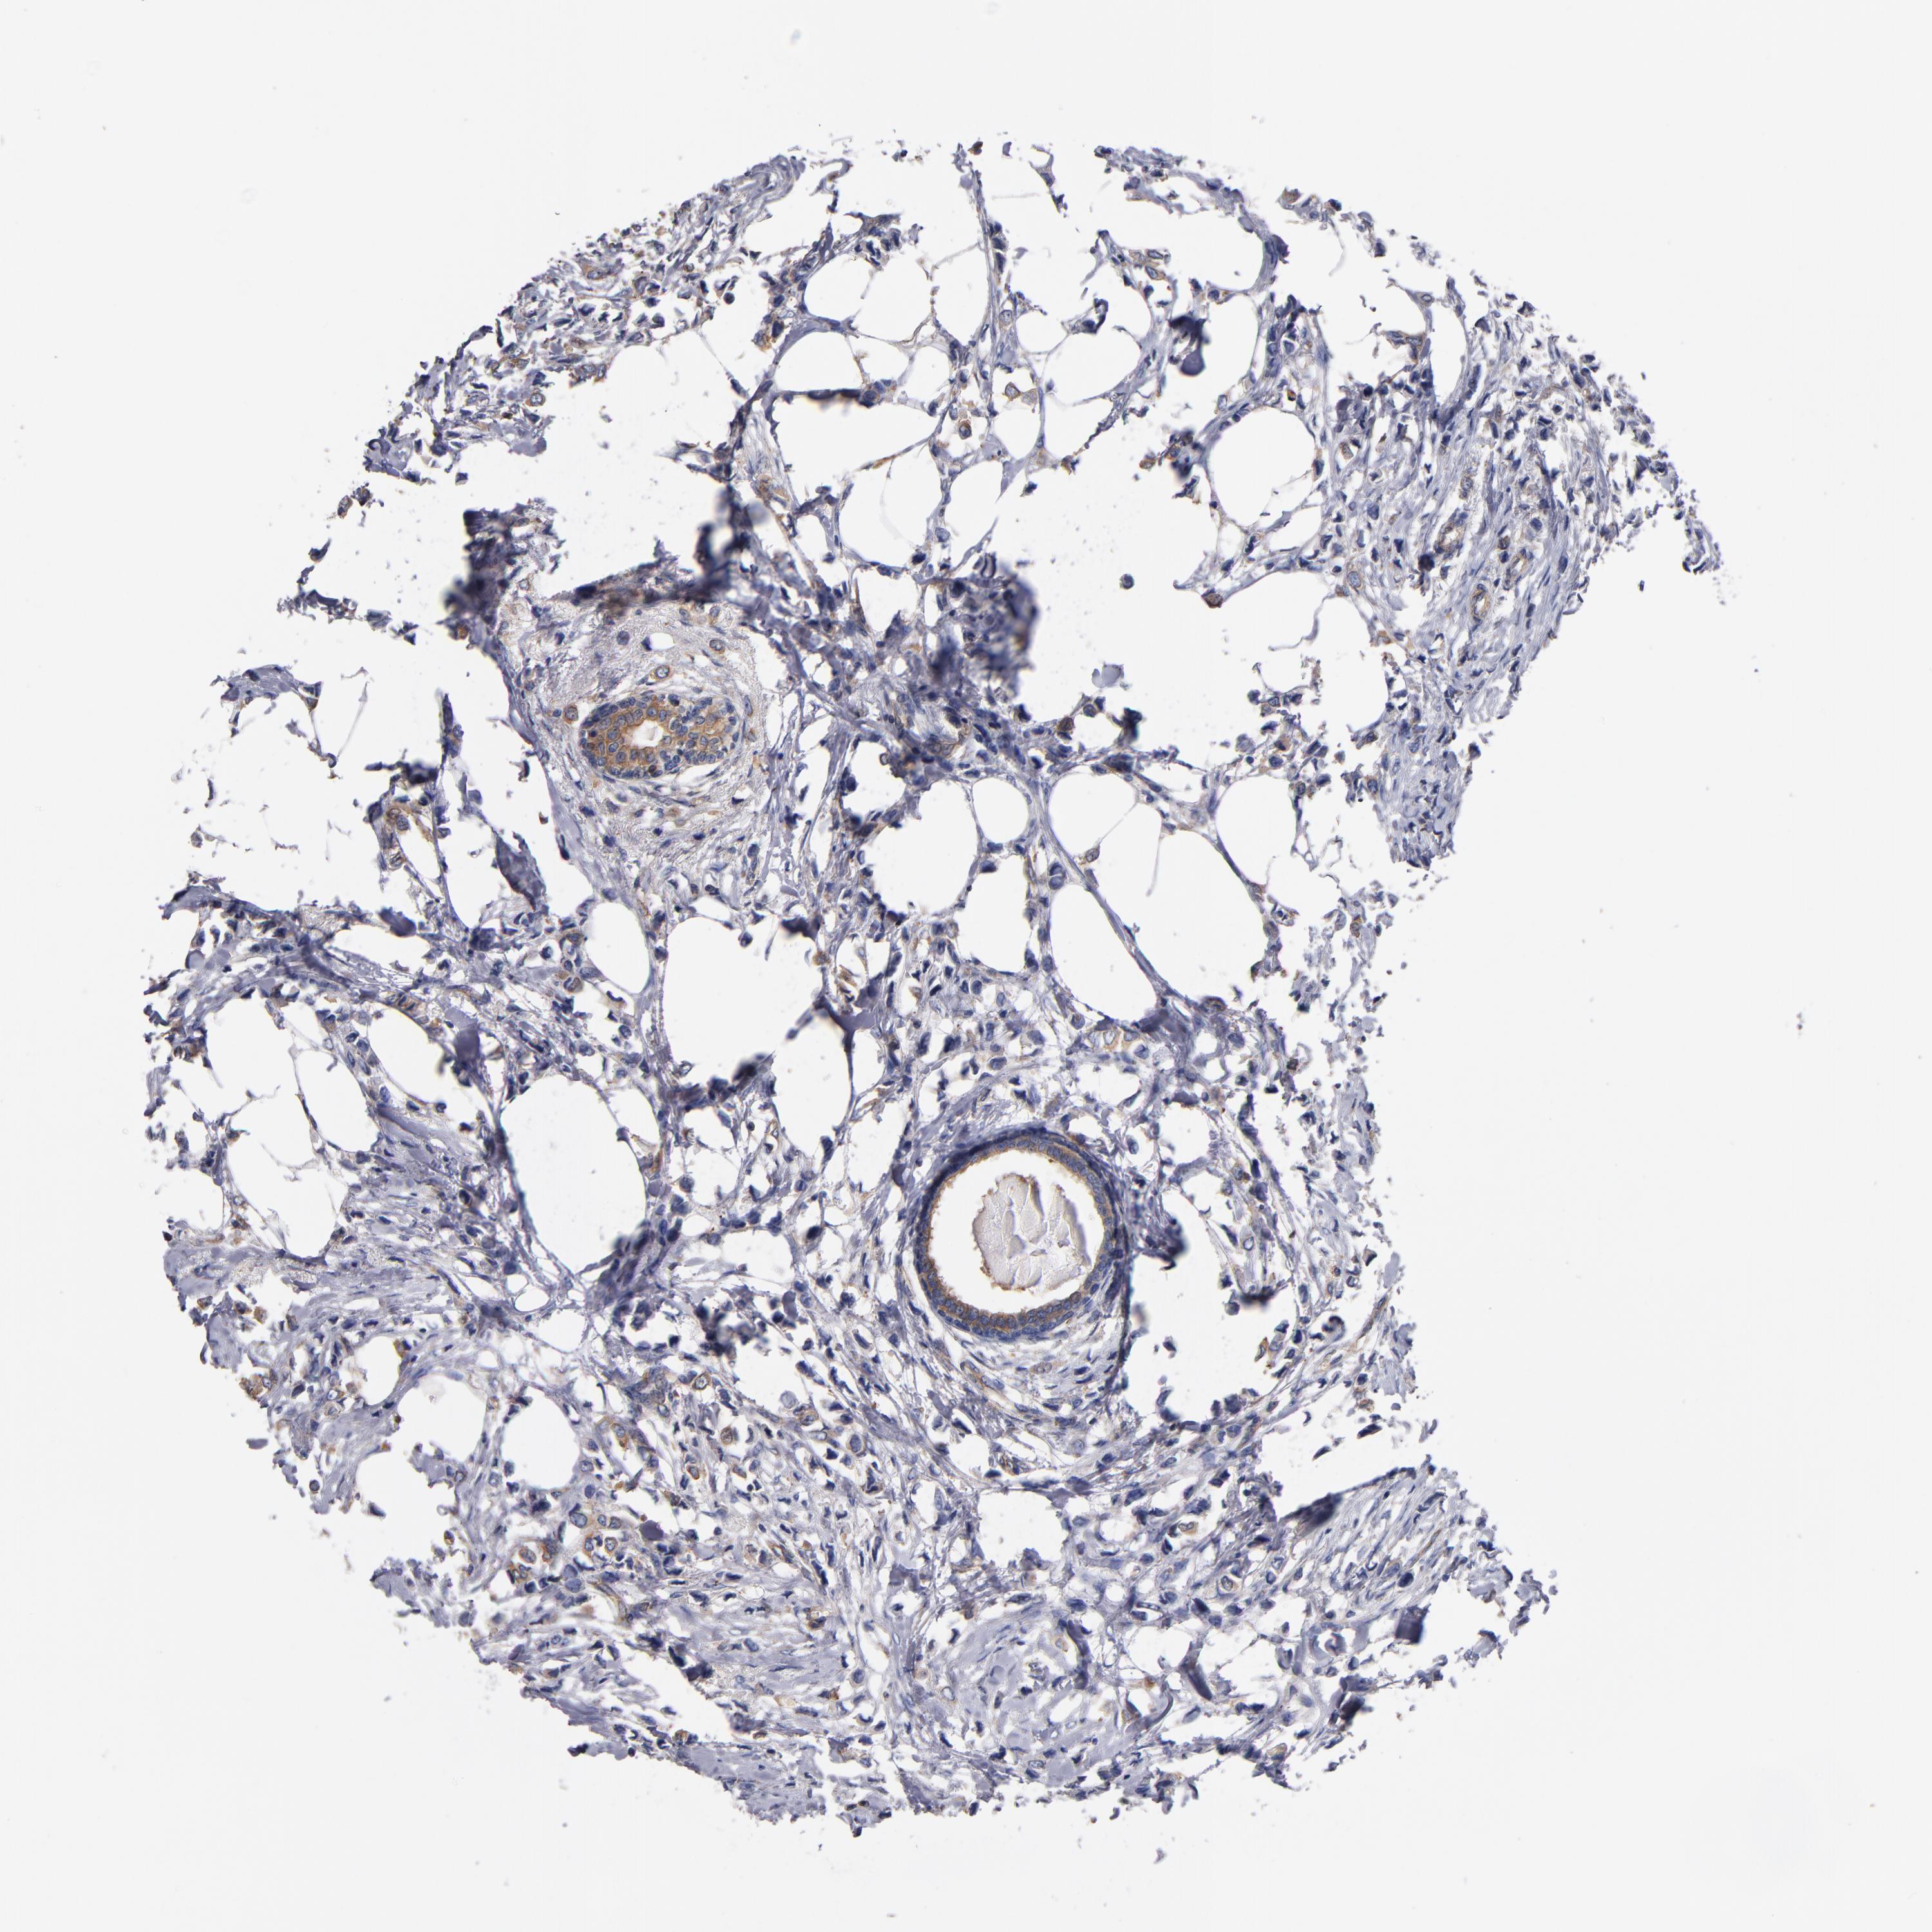

BRCA TCGA BRCA VALIDATION PROTEIN EXPRESSION

ANTIBODIES

AND

VALIDATION